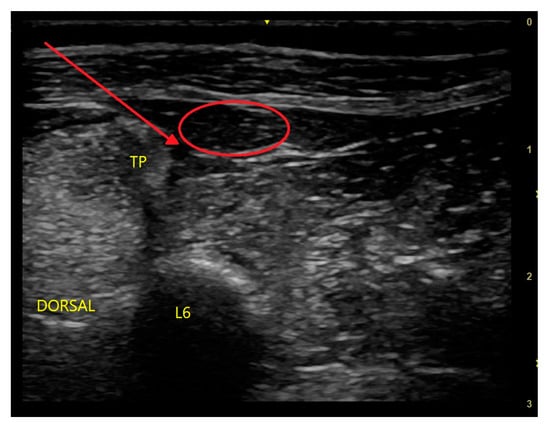

7.2. Brachial Plexus Block

- Campoy, L.; Bezuidenhout, A.J.; Gleed, R.D.; Martin-Flores, M.; Raw, R.M.; Santare, C.L.; Jay, A.R.; Wang, A.L. Ultrasound-guided approach for axillary brachial plexus, femoral nerve, and sciatic nerve blocks in dogs. Vet. Anaesth. Analg. 2010, 37, 144–153. [Google Scholar] [CrossRef]

- Akasaka, M.; Shimizu, M. Comparison of ultrasound-and electrostimulation-guided nerve blocks of brachial plexus in dogs. Vet. Anaesth. Analg. 2017, 44, 625–635. [Google Scholar] [CrossRef] [PubMed]